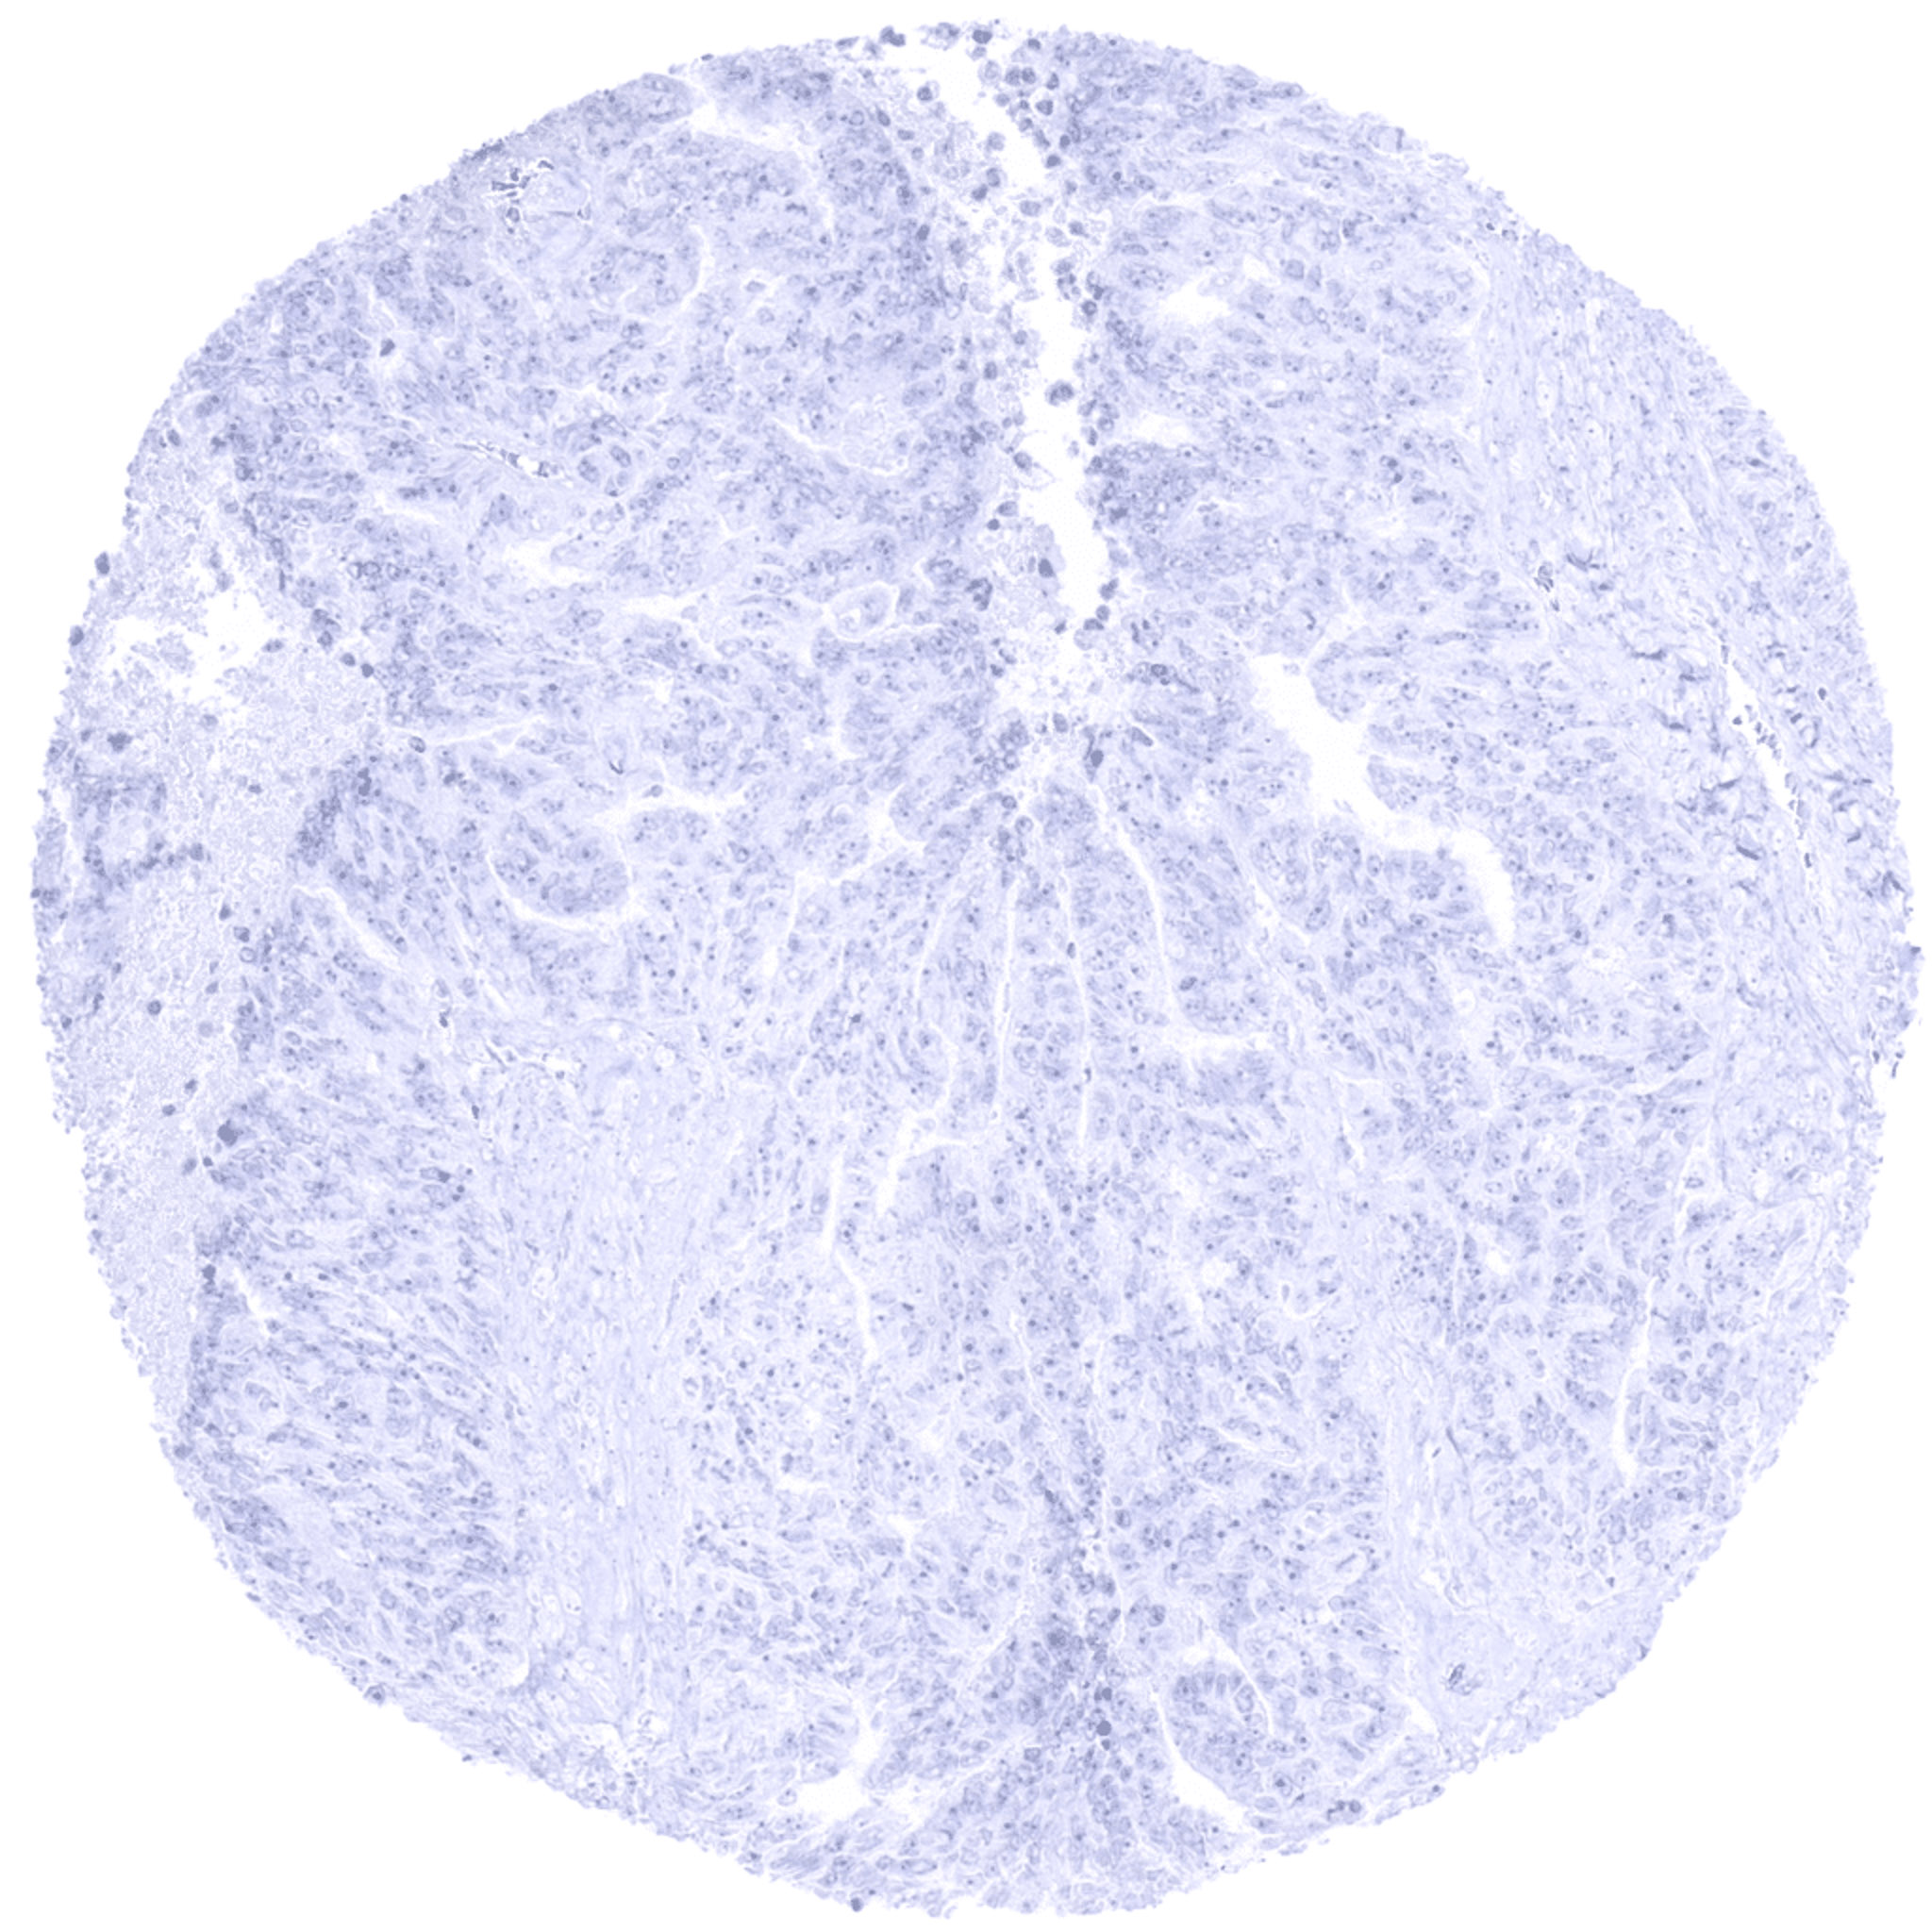

Kidney- S100P negative clear cell renal cell carcinoma.